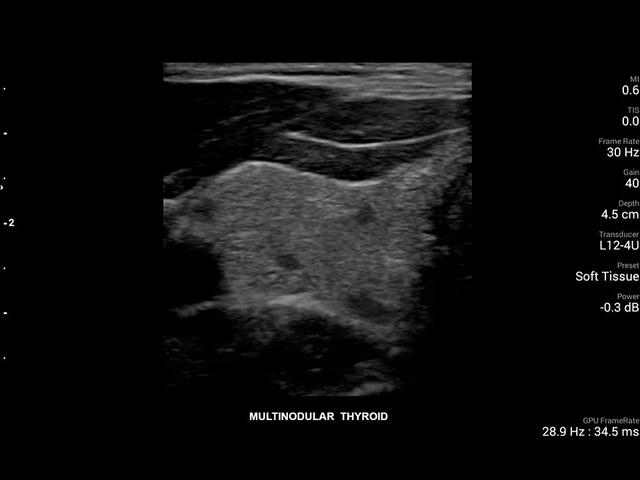

• Линейный УЗИ датчик Philips L12-4